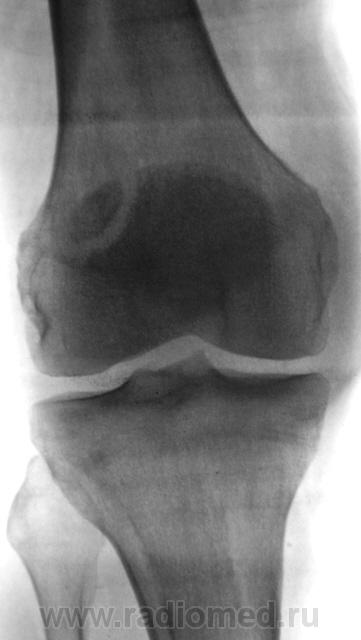

перелом надколенника( редко такой встречается) препателярная гемабурса, гемартроз, сильно пострадала суставная поверхность надколенника

Наверно все таки пателля бипартита. Представить, чтобы так красиво и ровно откололось - трудно... А мягкотканный компонент знатный...

Сам думал о "бипарцита", кстати, недавно был случай с "трипарцита". Но в данном случае был в растерянности, клиника "зашкаливает", конечно, возможно из-за мягкотканного компонента.

в литературе пишеться что пателя бипартита, чаще двустороняя и бессимптомная.. А что в анамнезе?

Травма накануне.

В минус травме говорит такая "красивенькая форма" отломка? НО при бипарите про мягкотканный компонент я данных ненашел..